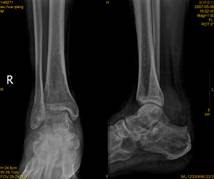

跟骨骨折影像病人有典型的外傷史,患足承重困難和足跟疼痛,局部觸痛、腫脹和皮下淤血斑亦多明顯。在較嚴重的壓縮骨折時,除可見到足後跟的高度變低和足跟橫徑變寬以及外踝下部正常凹陷消失外,距下關節話動亦完全喪失。但跟骨周邊骨折僅有局部腫脹及壓痛,而距下關節活動範圍多屬正常。x線正、側、軸位片可明確跟骨的結節關節角和其橫徑寬度的改變。

影像學表現

(1)跟骨前突骨折。

(2)跟骨結節的垂直骨折。

(3)載距突骨折。

(4)跟骨壓縮性骨折。

(5)跟骨粉碎性骨折。